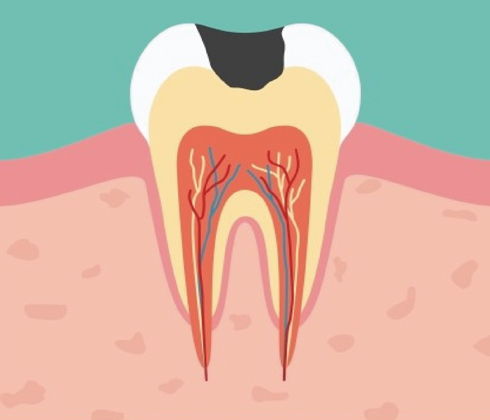

방치된 충치의 진행속도는 매우 빠릅니다.

단계가 진행 될 수록 치아 삭제량이 더 많아집니다.

단계가 진행 될 수록 치료 비용이 더 비싸집니다.

단계가 진행 될 수록 치료기간이 더 길어집니다.